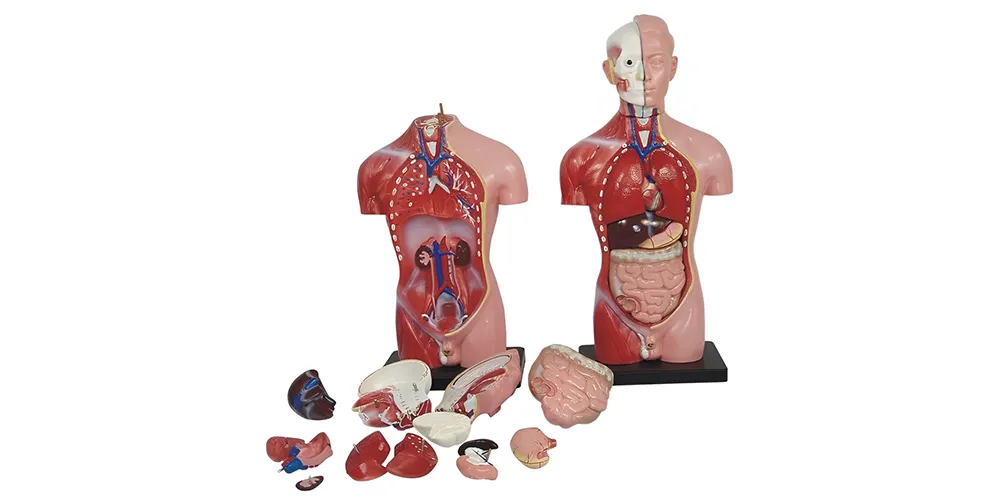

مولاژ، به عنوان یک ابزار آموزشی و پزشکی، نقش بسیار مهمی در آموزش و تحقیق دارد. این مدلها به صورت دقیق و واقعگرایانه ساختارهای مختلف بدن یا اعضای خاص را نمایش میدهند و به کاربران این امکان را میدهند که با جزئیات آناتومیکی آشنا شوند. مولاژها معمولاً از مواد با کیفیت بالا ساخته میشوند که امکان مشاهده دقیق و واضح جزئیات را فراهم میکند. استفاده از این مدلها در محیطهای آموزشی مانند مدارس پزشکی و دانشگاهها، به دانشجویان کمک میکند تا مفاهیم پیچیده را بهتر درک کنند. علاوه بر این، پزشکان میتوانند از مولاژها برای توضیح وضعیتهای پزشکی و درمانی به بیماران استفاده کنند، که به درک بهتر آنها از مشکلات و روشهای درمان کمک میکند. مولاژها به دلیل قابلیت تفکیک و مونتاژ، امکان بررسی و آموزش در مورد بخشهای مختلف یک عضو را فراهم میکنند. این ابزارها به خصوص در آموزش عملی و تحقیق، ارزش زیادی دارند و به افزایش دقت و کیفیت آموزش و تحقیقات پزشکی کمک میکنند.

مولاژها به طور کلی ماکتها یا مدلهای سهبعدی هستند که برای نمایش دقیق بخشهایی از بدن انسان، حیوانات یا حتی اشیای غیرزنده طراحی میشوند. این ابزارها به دلیل شباهت زیاد به نمونه واقعی، امکان آموزش عملی و بصری را فراهم میکنند. در حوزه پزشکی، مولاژها برای آموزش آناتومی، شبیهسازی جراحی، تمرین تکنیکهای درمانی مانند تنفس مصنوعی، بخیه زدن یا زایمان و حتی نمایش آسیبهای ساختگی برای آموزش تیمهای اورژانس استفاده میشوند. در طراحی مد، مولاژ به تکنیکی اطلاق میشود که در آن پارچه مستقیماً روی مانکن یا بدن مدل شکل داده میشود تا لباسی با تناسب دقیق و خلاقانه تولید شود. این روش بهویژه در طراحی لباسهای اوتکوتور و مجلسی کاربرد دارد. مولاژها همچنین در زمینههای باستانشناسی و هنر برای بازسازی آثار تاریخی یا ساخت ماکتهای نمایشی به کار میروند.

- مولاژهای کامل بدن: مدلهایی که تمام بخشهای بدن انسان را به طور کامل و تفصیلی نمایش میدهند.

مولاژ پزشکی ابزارهای آموزشی حیاتی در علم پزشکی و علوم زیستی هستند. این ابزارها به منظور آموزش و مطالعه ساختارهای آناتومیکی و فیزیولوژیکی بدن انسان طراحی شدهاند و برای پزشکان، پرستاران، دانشجویان پزشکی و محققان کاربرد دارند. مولاژها معمولاً به صورت مدلهای سهبعدی از اعضای مختلف بدن، از جمله اعضای داخلی و خارجی، ساخته میشوند و به گونهای طراحی شدهاند که جزئیات دقیقی از ساختارهای بدن را نمایش دهند.

ماکت پزشکی به مدلها و ابزارهایی اطلاق میشود که برای نمایش و آموزش ساختارها و عملکردهای مختلف بدن انسان طراحی شدهاند. این ماکتها، که معمولاً در آموزشهای پزشکی و بهداشتی کاربرد دارند، به دانشجویان، پزشکان و محققان کمک میکنند تا درک عمیقتری از آناتومی و فیزیولوژی بدن انسان پیدا کنند.

مولاژهای پزشکی شامل انواع مختلفی از ابزارهای آموزشی هستند که به نمایش قسمتهای مختلف بدن انسان، مانند قلب، کبد، و سیستمهای دیگر میپردازند. این مولاژها میتوانند به صورت مدلهای ساده یا پیچیده و با جزییات دقیق طراحی شوند تا به کاربر کمک کنند ساختارهای داخلی بدن را بهتر بشناسد و تفاوتهای آناتومیکی را درک کند.